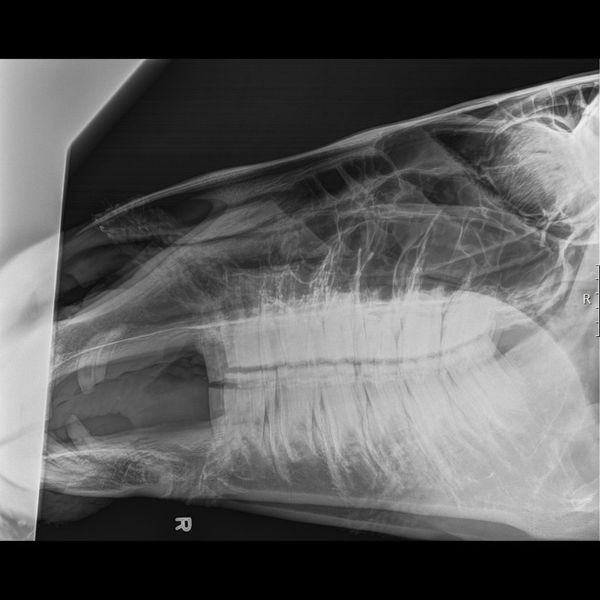

Seeing the Soft Stuff: Equine Musculoskeletal Ultrasound

While X-rays see through soft tissue, equine musculoskeletal ultrasound focuses entirely on it. If your horse has a "bowed" tendon or a swollen ligament, ultrasound is our most powerful tool. It uses high-frequency sound waves to create real-time images of fibers and fluid. This is the primary method for horse soft tissue injury diagnosis, allowing us to map the exact location and severity of a tear. It also helps us monitor the healing process, ensuring you don't return your horse to work too early and risk re-injury.